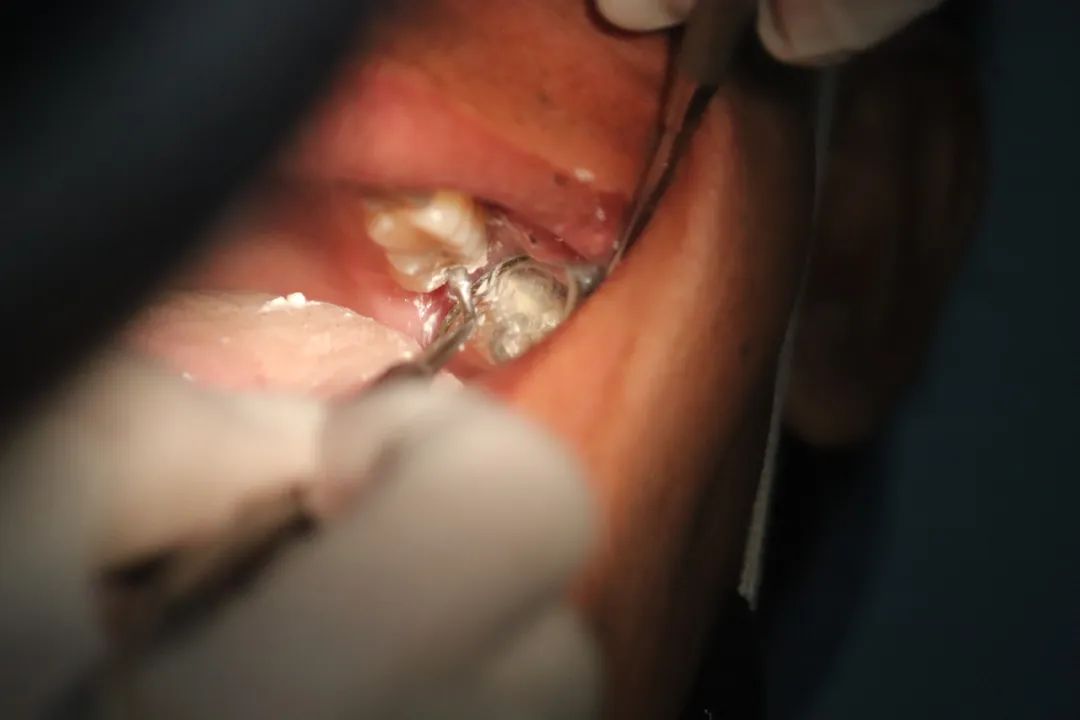

等到发现时,它已“默默地”向深部组织浸润,侵犯深层黏膜以及骨组织,引起牙齿松动,口腔内肿块还会出现溃烂、出血、剧烈疼痛,并且容易发生颈部淋巴结以及全身肿瘤转移,甚至最终危害生命。

从颜色上看:口腔黑色素瘤表现为明显的蓝黑色结节状肿块。从生长速度看:口腔黑色素瘤生长速度十分迅猛,颜色加深,并向四周扩散生长。

从形态上看:一般表现为斑点或者结节状,表面常溃烂。

从发病位置看:口腔恶性黑色素瘤大多数出现在上牙龈以及硬腭,也有部分病例病变位置出现在颊部、舌部以及唇部。